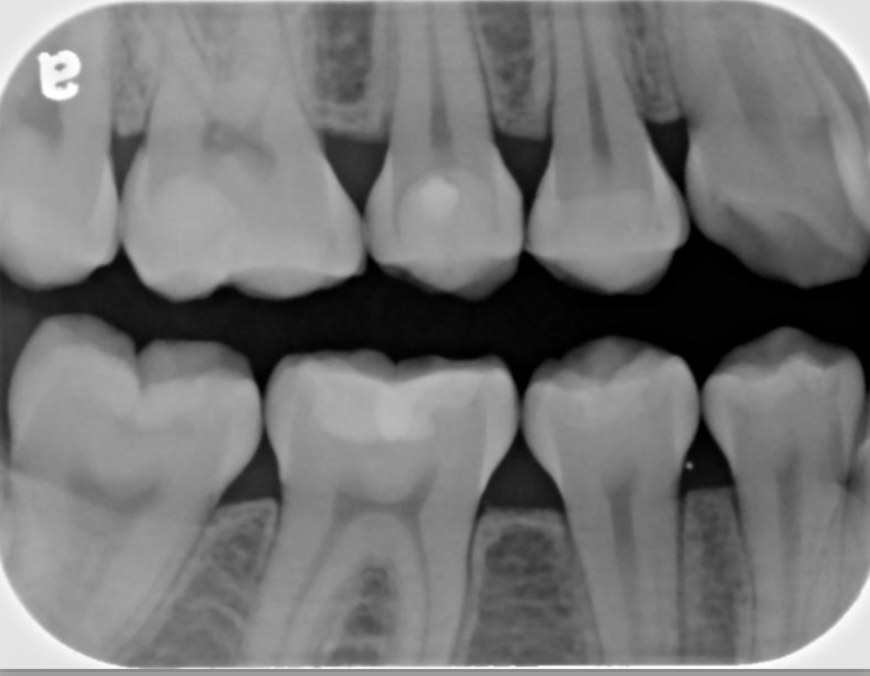

20

Q

What type of radiograph is seen in the following image?

A

Horizontal bitewing

21

Does the following image show correct or incorrect angulation for a bitewing?

Correct